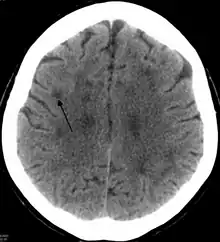

TC mostrando leucoencefalopatía probablemente debida a una isquemia de pequeños vasos. La flecha apunta solo a una de las muchas áreas.